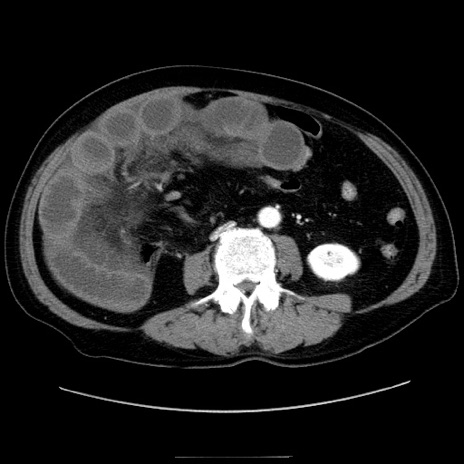

症例30(横断像)

【症例】80歳代男性

【主訴】臍周囲痛

【現病歴】約6時間前から臍下部痛が出現。次第に腹部膨隆・背部痛も生じてきたため来院。背部痛の場所は変化しない。

【身体所見】意識清明、BT 36.3℃、BP  131/87mmHg、P 87bpm、SpO2 100%(RA)、臍周囲自発痛・圧痛あり、反跳痛なし、自発痛部位に一致して板状硬あり、腹部膨隆、腸雑音減弱、CVA tenderness両側陰性。

【データ】WBC 19600、CRP 0.33